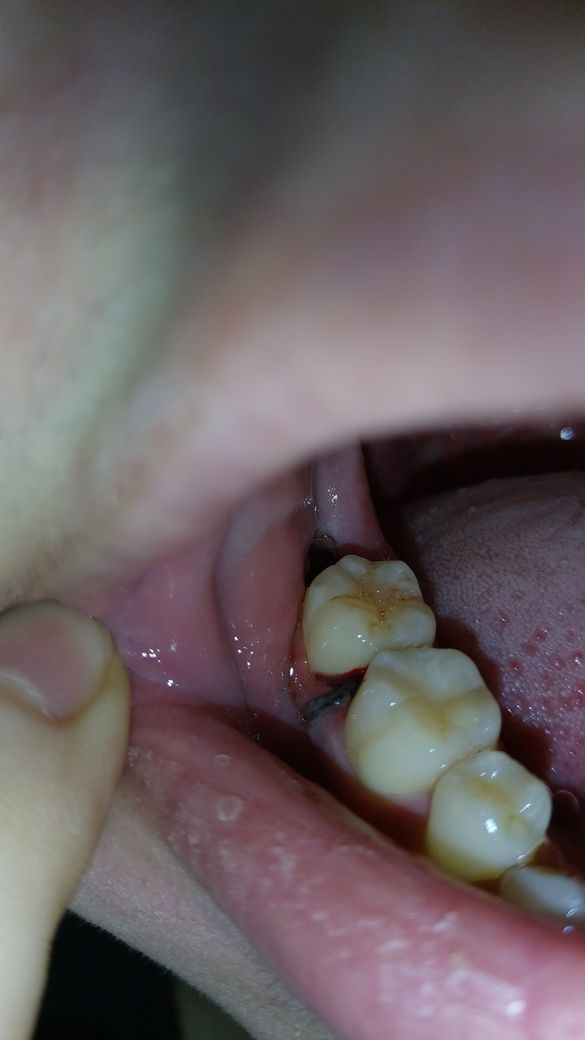

2월20일날 위 아래 사랑니 발치해서 5일째인데

방금 양치했는데 꿰맨곳에서 출혈이 살짝 있는거같은데 자연스러운 현상일까요 ? ㅜㅜ 그리구 입을 벌리거나 그러면 잇몸 꿰멘곳이 약간 걸리적거리는 통증이 있어요 평상시엔 통증 없구요 이것도 자연스러운걸까요..

발치 후 5일째라도 꿰맨 부위가 자극을 받으면 피가 조금 스며 나올 수 있으나 별다른 문제 되지 않습니

다. 사진으로 보아 피의 양도 많지 않으니 그냥 두면 저절로 없어집니다.

잇몸 주변 반응 및 부종 등으로 평가했을 때 정상적인 치료 과정으로 보여집니다. 발치 당시의 매복 정도가 심하다면 아직까지 출혈이 조금씩 나타날 수 있으며 연조직이 회복되는데는 2주 정도 시간이 걸릴 수 있습니다. 극심한 통증만 없다면 크게 걱정하지 않아도 됩니다.